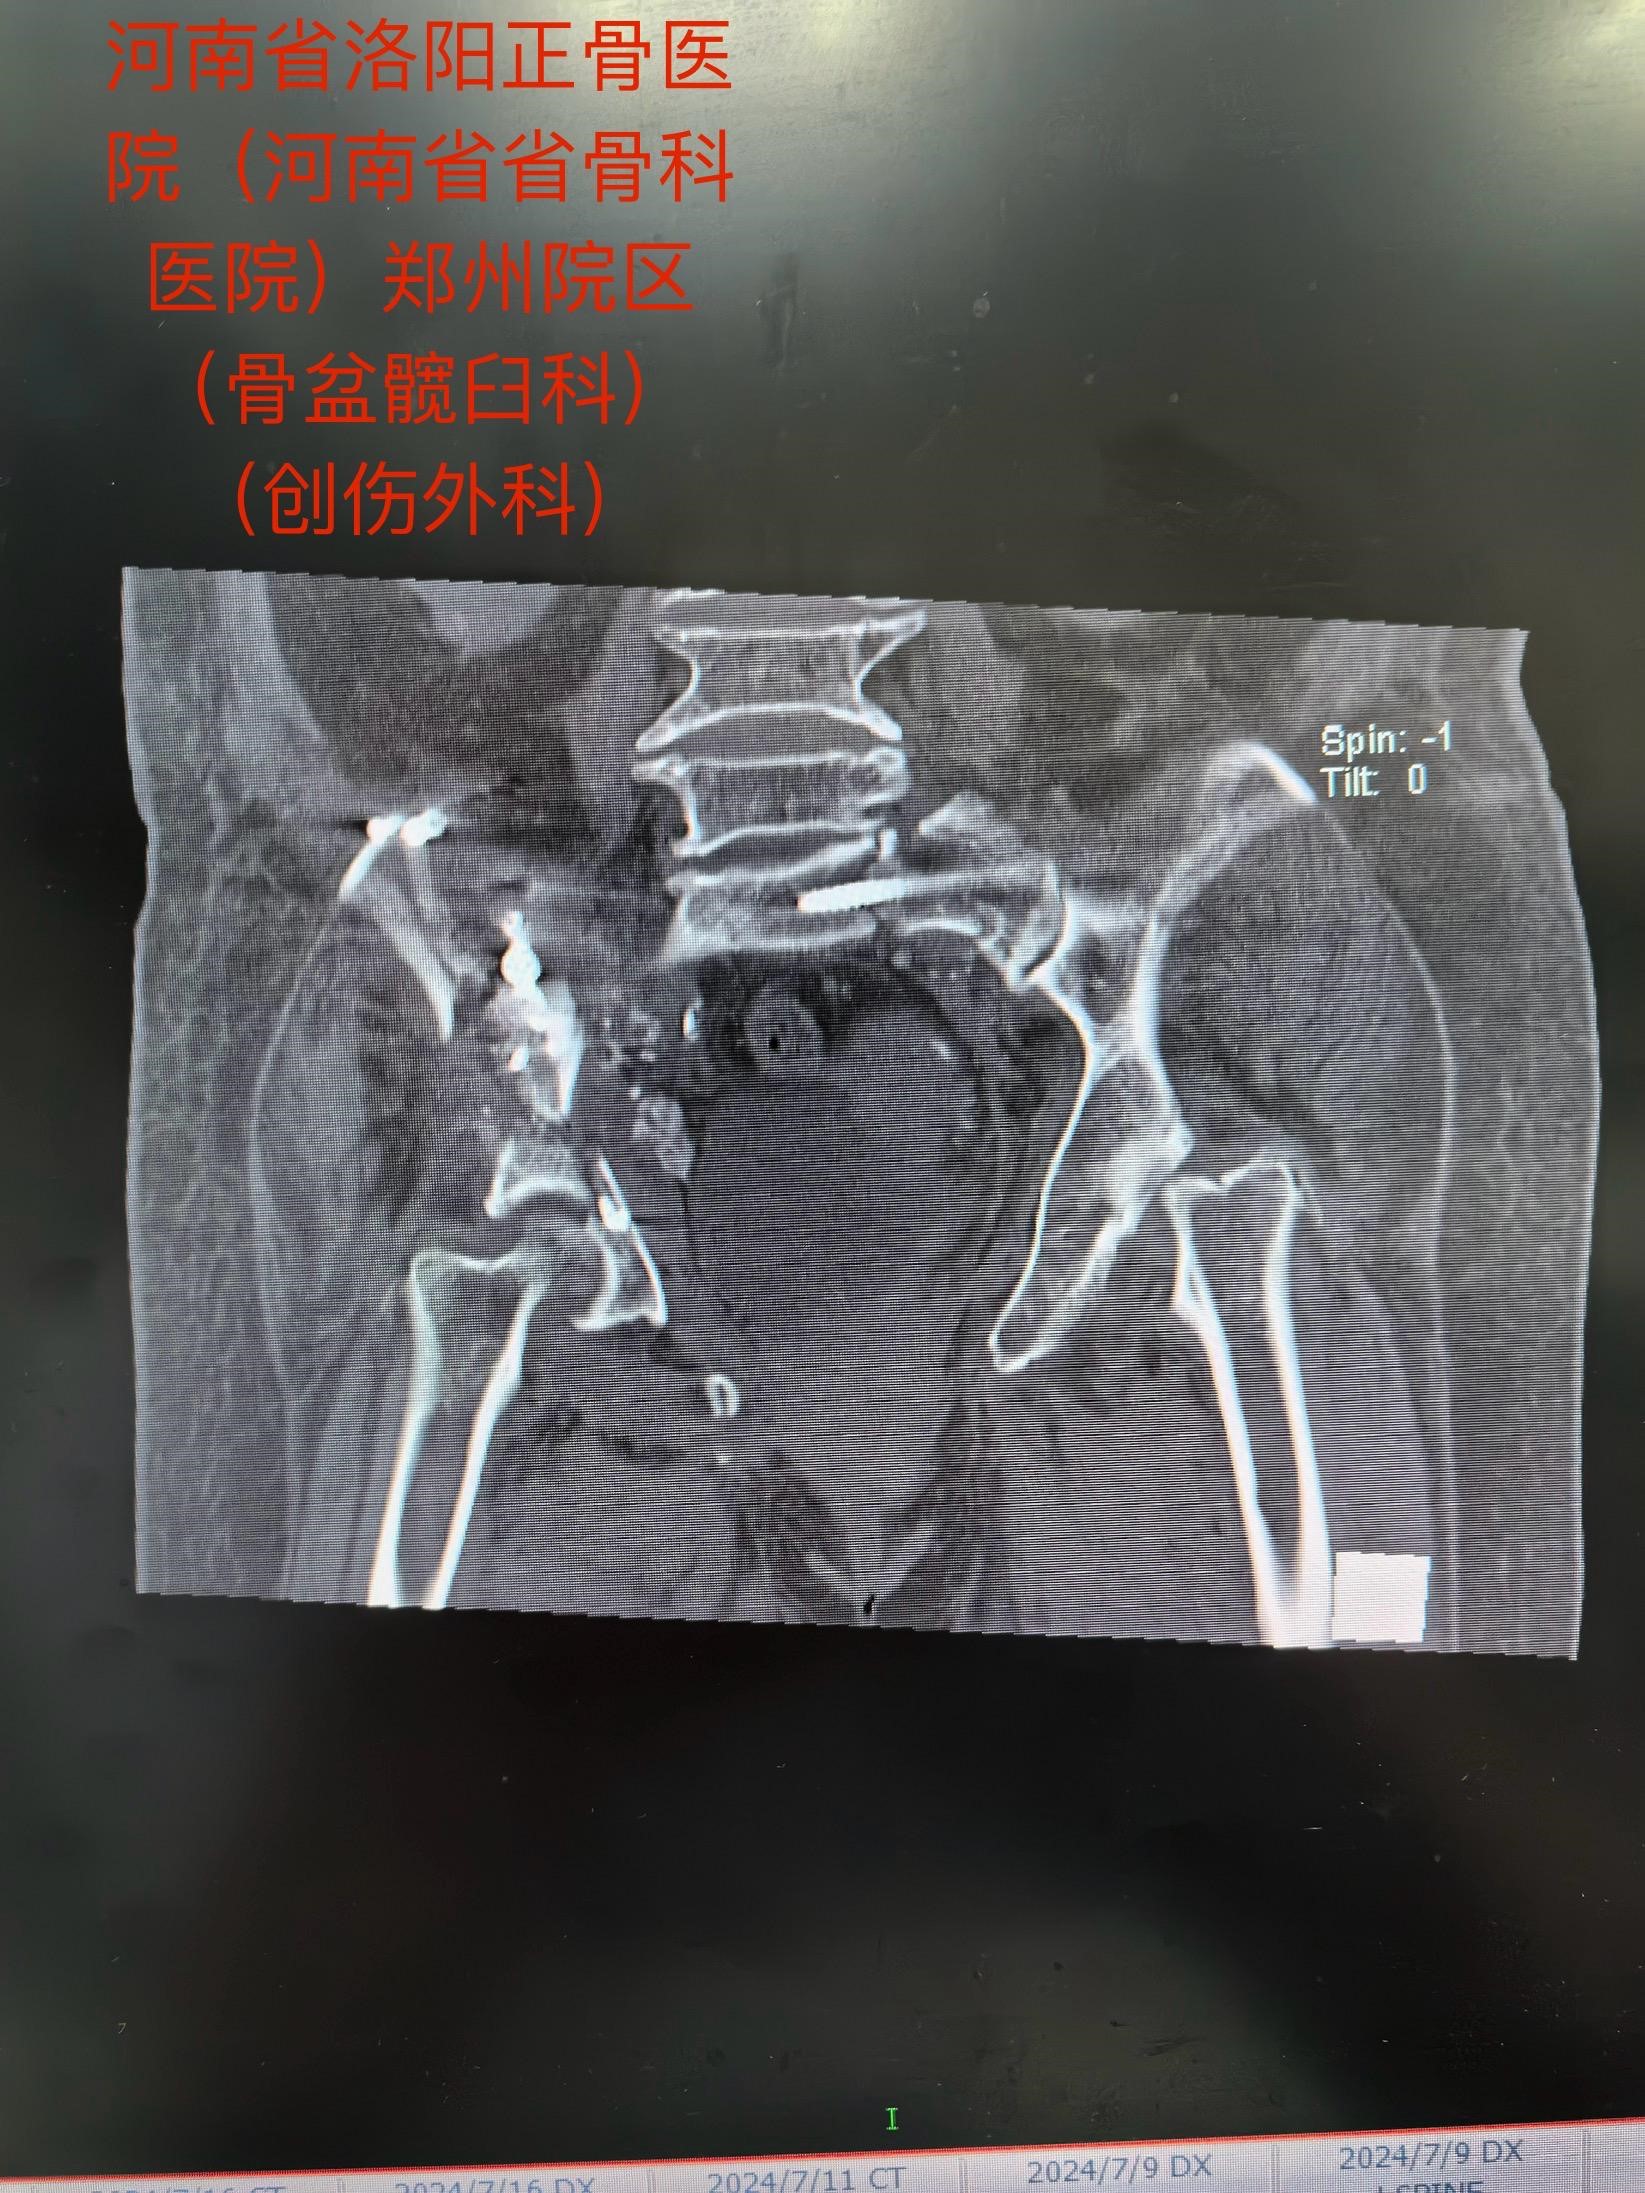

老人今年73岁,遭遇车祸后全身多处伤,在当地医院ICU治疗,生命体征平稳后,转入我院郑州院区。影像检查诊断:骨盆合并髋臼骨折,右侧髋臼双柱骨折……

马献忠主任积极倡导加速康复外科理念,对于老年骨盆髋臼骨折患者,他主张积极治疗。面对老人的复杂病情,马献忠主任积极组织多学科会诊,充分讨论,详细制定术前规划,为老人量身定制治疗方案。马献忠主任分两期进行手术:1期,右侧骨盆髋臼行单一髂腹股沟入路进行骨折复位及前后柱的固定。2期,进行左侧的微创骶髂螺钉固定骨盆后环。